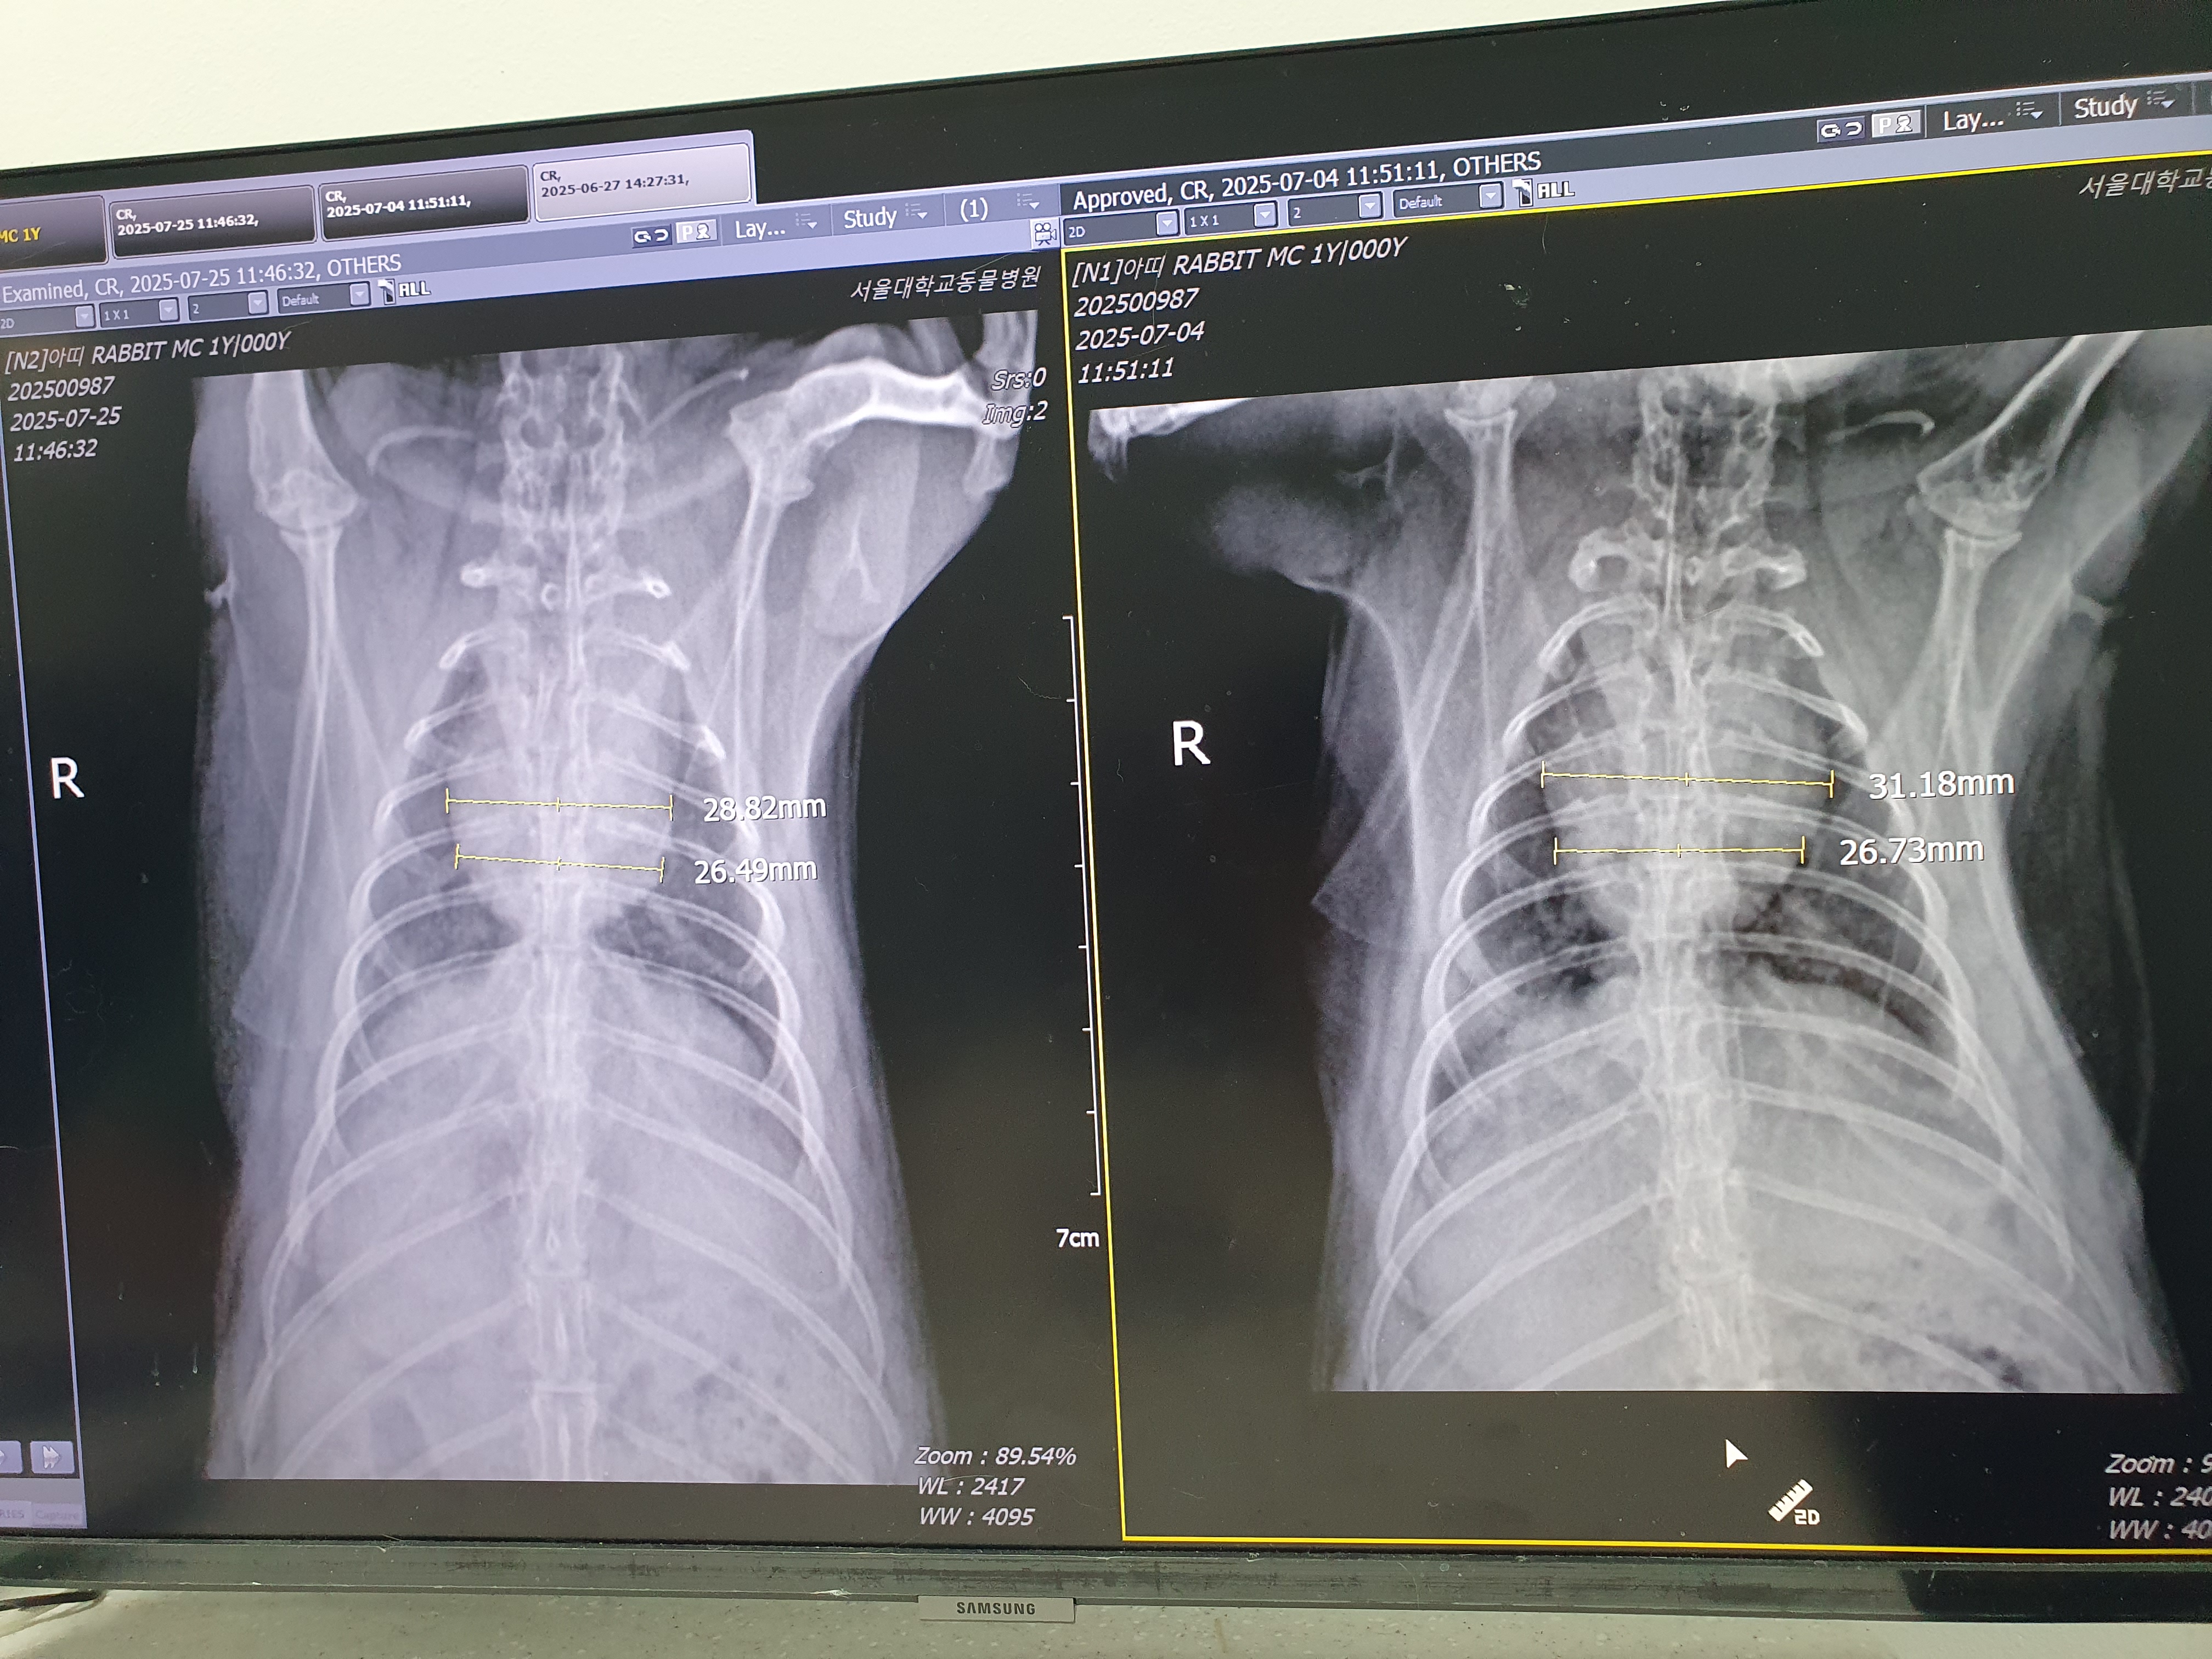

토끼보호연대의 꾸시꾸시 보호소에서 6월 16일 저녁 먹이반응 저조함을 발견하여 prokinetics와 진통제가 포함된 비상약 투여 후 17일, 18일까지 저조함 지속되어 피하수액 투여 후 19일 아침 서울대 응급실 경유하여 입원, 당시 체온 40도 조금넘었고 콧물이 보이고 엑스레이상 심장이 크고 폐주변 실질의 음영증가 소견.

7월 25일 서울대 재내원, 폐의 이상음영 거의 다 사라지고 심장 크기도 조금 줄어든 상태로 귀와 이빨도 무난하지만 몸무게는 약 100그람 정도 빠진 상태로 편식으로 인한 체중감소일 가능성 높아 토끼보호연대의 결정으로 하늘바람의집에서 퇴소함.